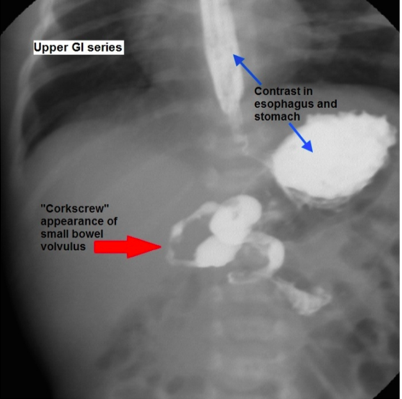

Midgut Malrotation

Incomplete counterclockwise rotation (eg, 180 degrees) will result in midgut malrotation. The cecum will rest in the right upper quadrant instead of the right lower quadrant (RLQ). Additionally, Ladd's (fibrous) bands connect the retroperitoneum in the RLQ to the right colon/cecum by passing over the second part of the duodenum, causing intestinal obstruction in the process. Obstruction manifests as bilious emesis during the first days of life. In addition, because the mesenteric base is abnormally narrowed, the mesentery is vulnerable to twisting around the superior mesenteric artery. The twisting, referred to as midgut volvulus, compromises intestinal perfusion and may lead to life-threatening bowel necrosis.